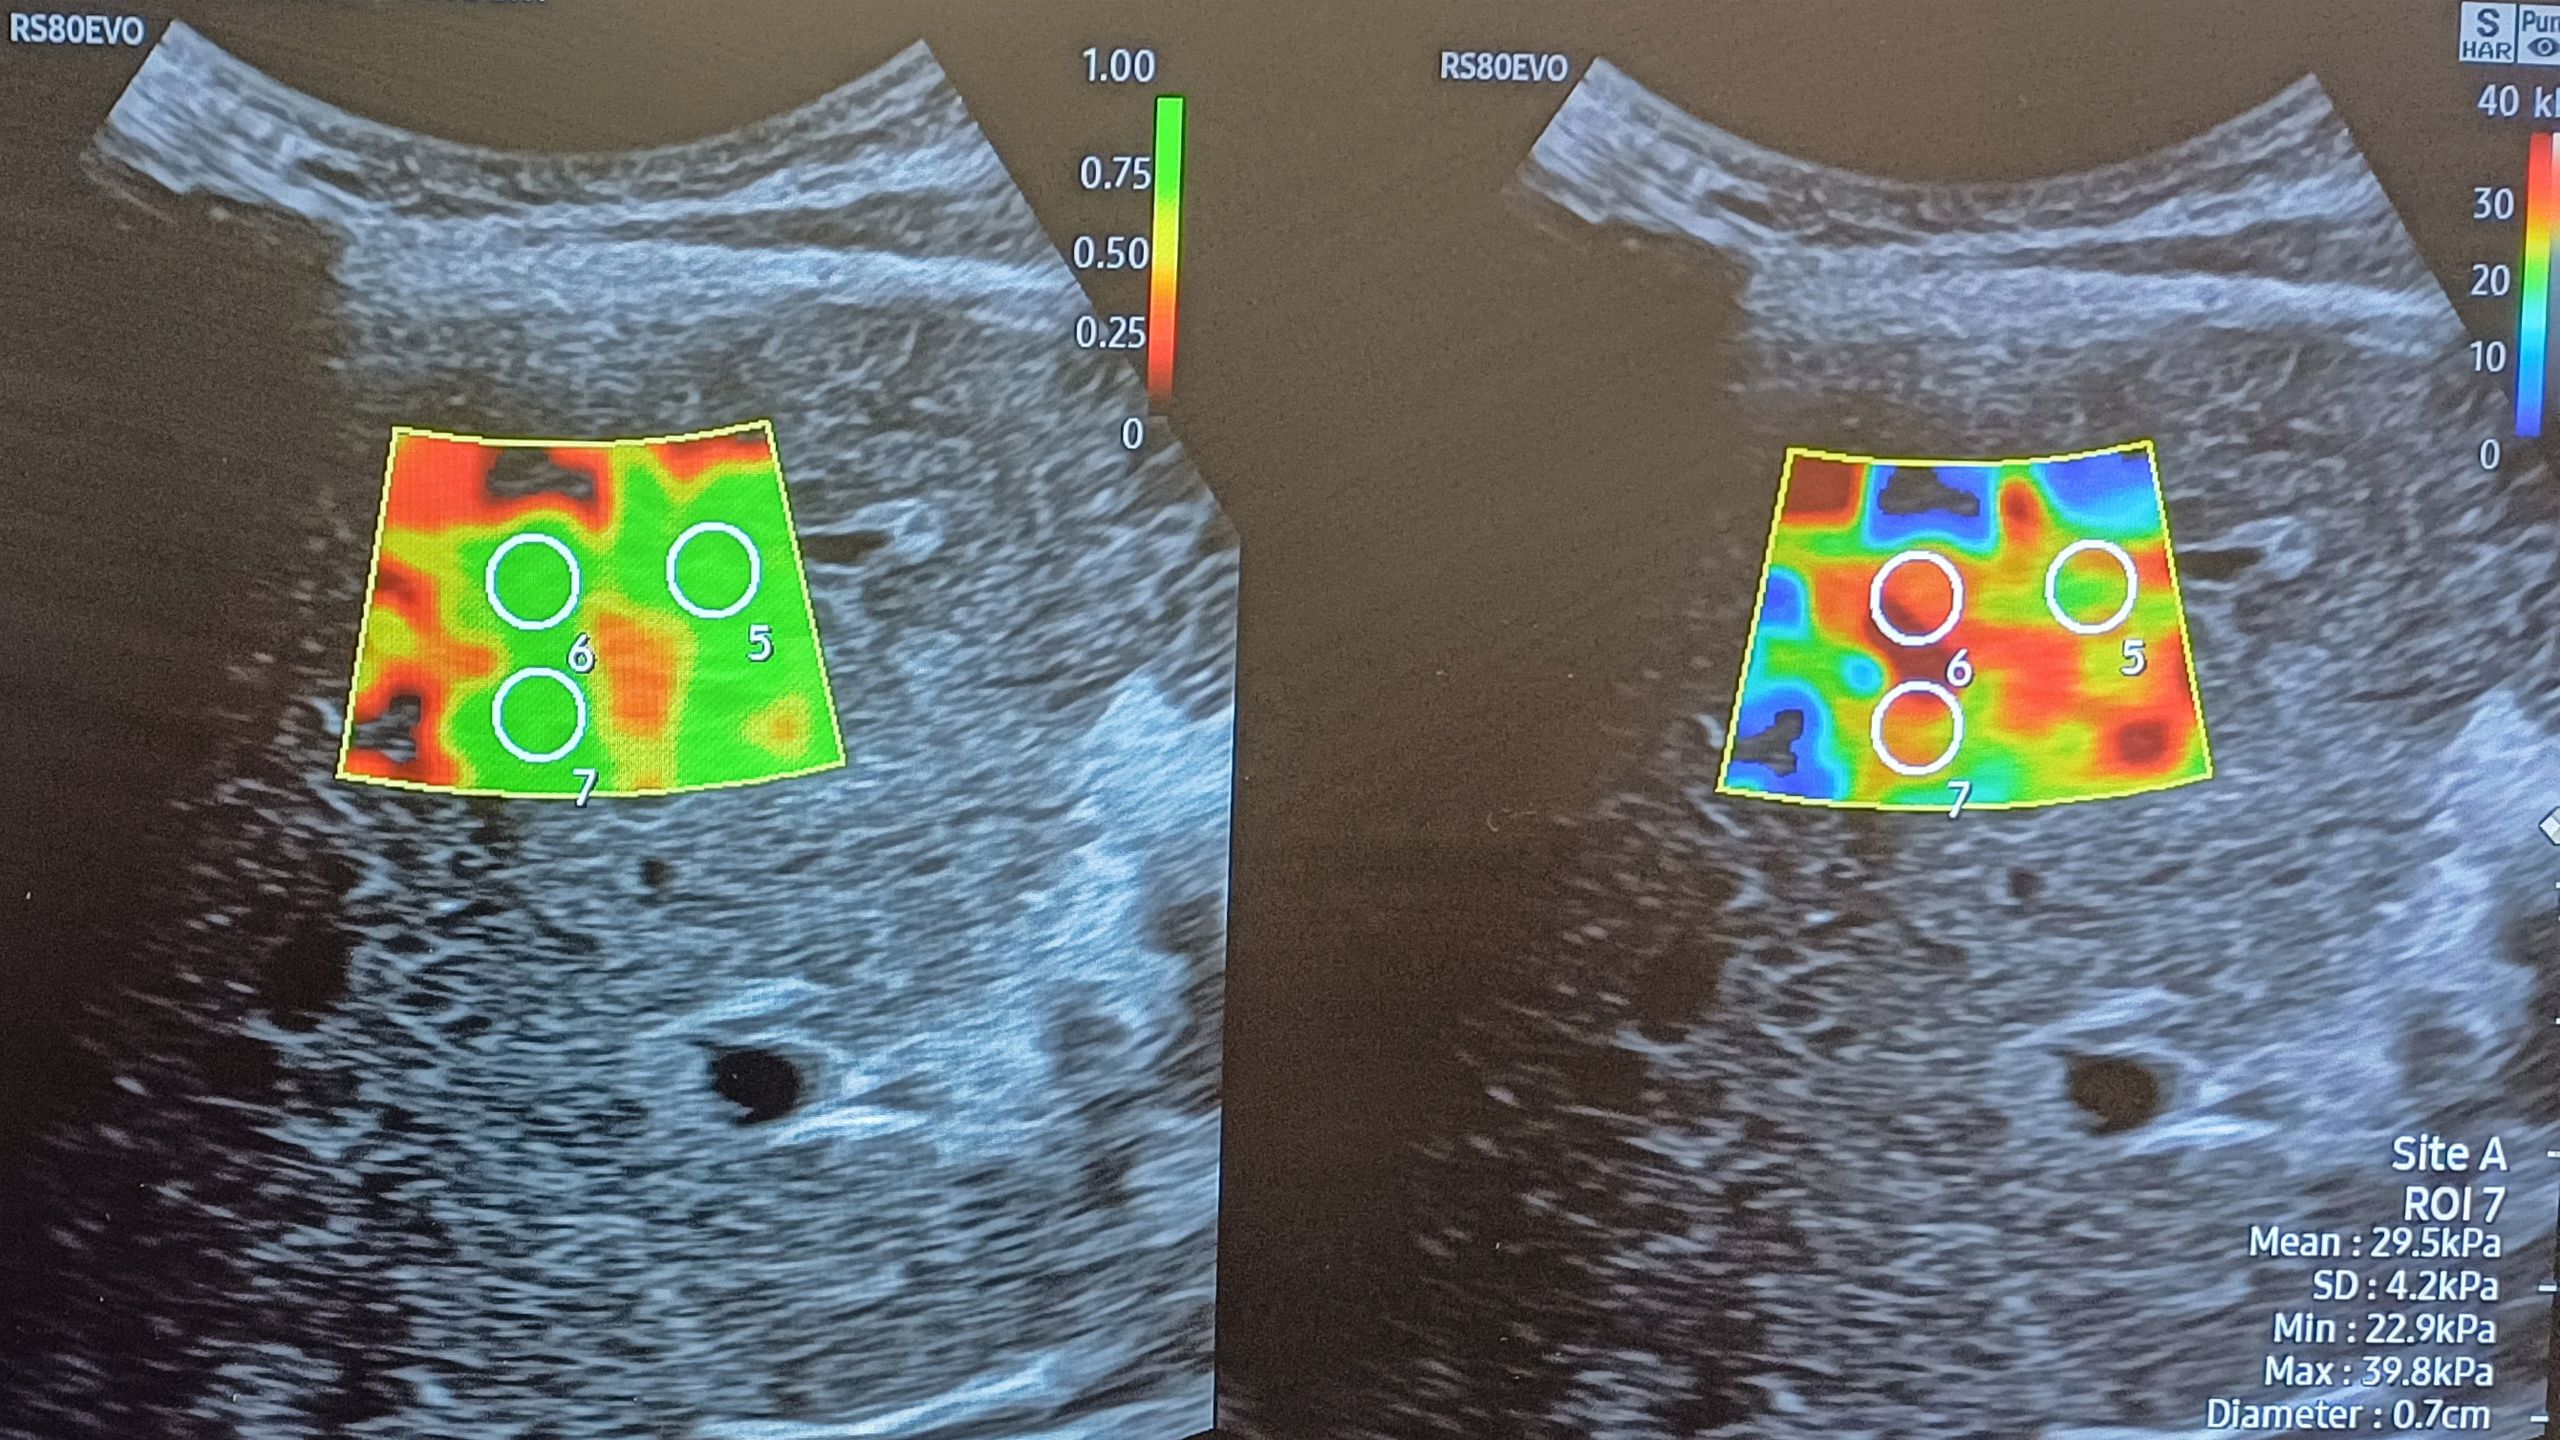

Hepatocellular carcinoma surveillance ultrasound

Radiographers at the Worcestershire Acute Hospitals NHS Trust have successfully implemented an ultrasound service for detecting one of the most common types of liver cancer, hepatocellular carcinoma.